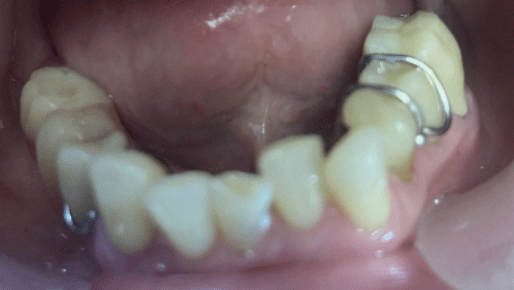

In recent years, we have replaced removable overdentures with a Mandibular Orthopedic Repositioning Appliance (MORA), also known as the Gelb appliance.4,5,7 This is a removable, diagnostic appliance that repositions the mandible by engaging the mandibular molars and some premolars bilaterally, while leaving the cuspids and incisors uncovered. The two sides are connected via a sublingual bar. This design is phonetically neutral and generally better accepted by patients (Fig. 1).

Fig. 1

Patients are instructed to wear the appliance consistently, removing it only during meals. The increased VDO changes the length of the masticatory muscle fibers, which in turn reduces muscle activity. Additionally, shifting occlusal contact toward the molars brings the load closer to the fulcrum—the TMJ—thereby reducing stress on the system.

After informed consent, Phase I began with delivery of a Gelb appliance (Fig. 3ABC), which was adjusted periodically until achieving the treatment VDO. Phase II involved stabilization at this VDO. Teeth 36, 35, 43, and 44 were prepared simultaneously, and impressions (Henry Schein VP MIX) and bite registration (Kopy ultra-fast VPS) were taken using the palatal jig.

Fig. 3A